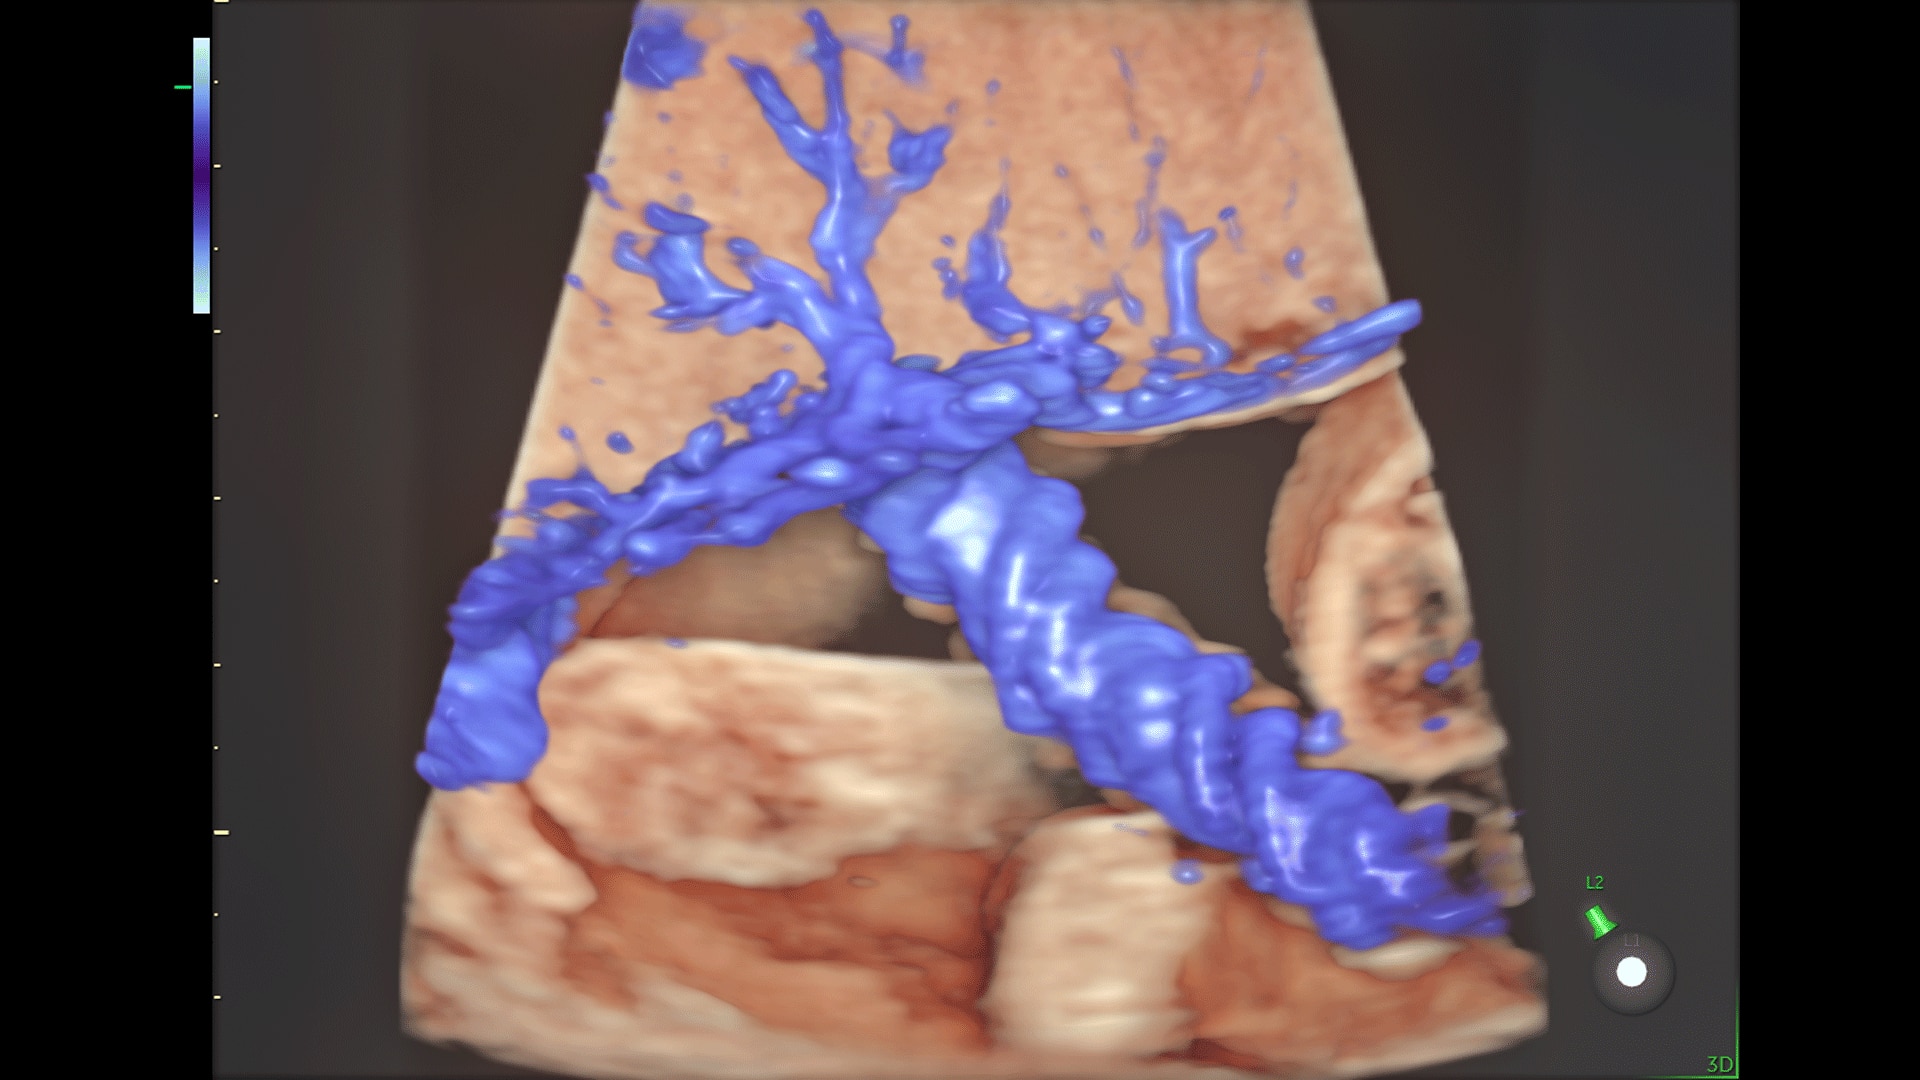

Amplify imaging performance and simplify scanning with our most advanced architecture

Extraordinary clarity and definition so you can focus on early detection and intervention.

Faster.Sharper. Clearer.

Faster.Sharper. Clearer.